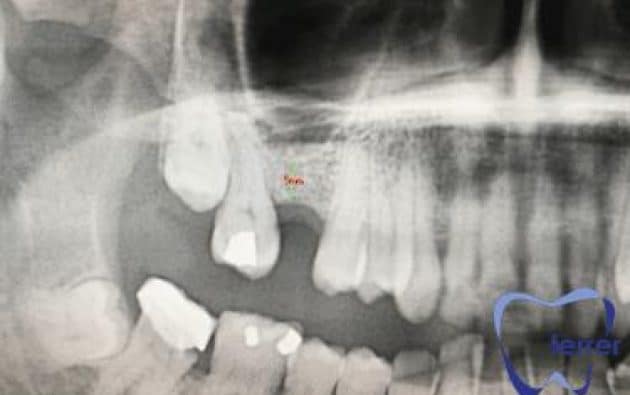

Durante esta valoración inicial, realizamos un escáner 3D o TAC dental de alta precisión que nos permite observar en detalle la cantidad y calidad del hueso disponible.

Esta imagen tridimensional nos ayuda a planificar el injerto con total seguridad, definiendo el volumen necesario y localizando estructuras anatómicas importantes como el nervio dentario o el seno maxilar.

Mediante revisiones clínicas y nuevas pruebas de imagen, confirmamos que la regeneración ósea avanza correctamente antes de programar la colocación del implante. Así garantizamos un resultado predecible, seguro y duradero.